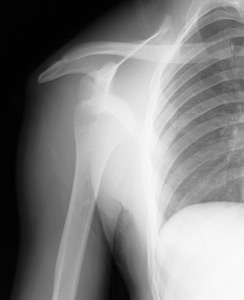

One of the four rotator cuff stabilizers of the shoulder, the infraspinatus is prone to active, latent and satellite trigger points. It attaches medially to the infraspinous fossa of the scapula and laterally to the middle facet of the greater tubercle of the humerus. It originates by fleshy fibers from its medial two-thirds and by tendinous fibers from the ridges on its surface. The fibers converge to a tendon that glides over the lateral border of the spine of the scapula and, passing across the posterior part of the capsule of the shoulder joint, is inserted into the middle impression on the greater tubercle of the humerus. It is an external (lateral) rotator of the glenohumeral joint and adductor of the arm. The infraspinatus and teres minor rotate the head of the humerus outward (external or lateral rotation); they also assist in moving the arm backward (extension of the glenohumeral joint). However, the infraspinatus is the major external rotator.

shoulder blade - Copyright – Stock Photo / Register Mark Common sense dictates that muscles need to contract and relax for movement to occur. Without this action system, we would be immobile. The problem is in how much and how well these muscle contractions occur. When muscles are affected with a trigger point, they become inherently tighter; sort of like tying a knot in a rope naturally shortens its original length. The presence of the knot and ensuing stiffness ultimately cause a loss in range of motion. This is exactly what happens to a muscle.